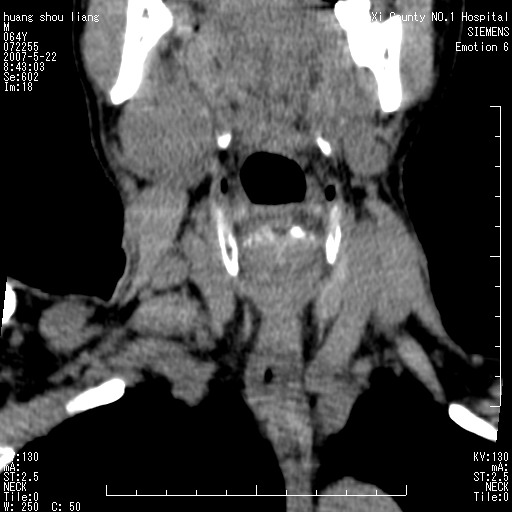

男性,64岁。颈部包块8年。最近增大。

对不起大家,可能是片子发太多有点乱,正常腮腺在下颌角的外侧,颌下腺在下颌体的中部内侧,本例在下颌角内侧偏下,和腺体一点关系都没有,从vrt和mpr上可以很明显看出来,再者肿块是好多粘连在一块的,大家在仔细看看,左侧可能也是吧,我还是考虑为肿大的淋巴结融合在一块,但性质??????

右侧腮腺下部均匀软组织密度肿块,外形不规则,与周围组织分界清晰,考虑右侧腮腺混合瘤或多形性腺瘤。

大家好,病理结果出来了,如大家所说,颌下腺混合瘤。

唉,解剖没学好吧,我诊断错了,不过还是有些不理解回去我在多看看书,谢谢大家的参与,以后我还会奉献好的病例。